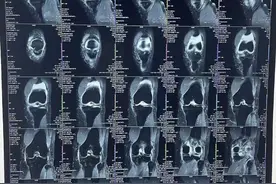

随着互联网诊疗的普及,很多人在远程问诊时都会遇到想把检查结果拍个照片发给医生看,以便咨询的情况。不过,拍摄CT、核磁共振、X光片等影像片子可是技术活。很多人苦恼于黑乎乎的胶片不容易清晰对焦,常常把很模糊的照片发给医生,影响医生对病情的判断。

随着互联网诊疗的普及,很多人在远程问诊时都会遇到想把检查结果拍个照片发给医生看,以便咨询的情况。当需要拍摄CT、核磁共振、X光片等影像片子,黑乎乎的胶片如何拍都不好对焦,很多人苦恼于胶片的拍摄技巧,常常把很模糊的照片发给医生,影响医生对病情的判断。

一、上传影像学片子的重要性所有医生在解答患者咨询时,都是以检查片子为依据,而不是检查报告。因为不同医生看同一张片子,会因为水平、经验不同,得出的结果不会完全一样。而且影像学检查的结果对某些疾病的诊断和治疗非常重要,是医生决定治疗方案的参考因素之一。